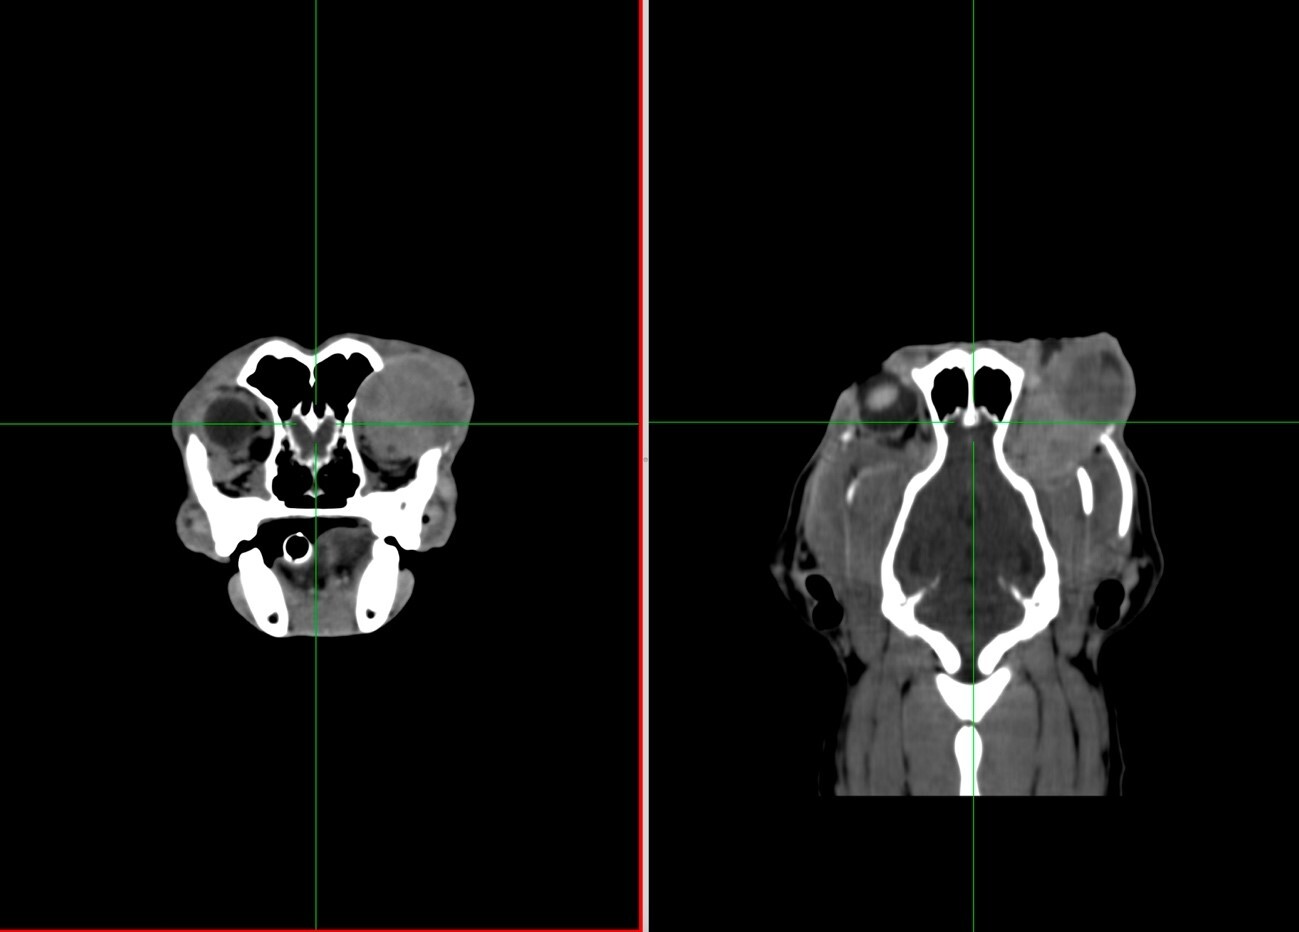

症例④:眼球の腫瘍(軟部組織肉腫)

軟部組織肉腫とは

高齢の犬に多く発生する悪性腫瘍のひとつです。根が深く広いことから再発率が非常に高いといわれております。そのため、外科的処置を行う場合は、腫瘍の部分を大きく切除する必要があります。

| 種類 | 犬 柴 |

|---|---|

| 年齢 | 14歳(当時) |

| 主訴 | 半年前から眼に腫瘤ができているとのことで来院 |

| 眼球摘出 | 眼球と腫瘍の全体像を把握するために、CT検査を行いました。 |

CT検査は「調べる」という目的だけではなく、処置をする上でも活用する場合があります。また、飼い主様にもよりわかりやすく、状態・処置方法などをご説明することが可能です。